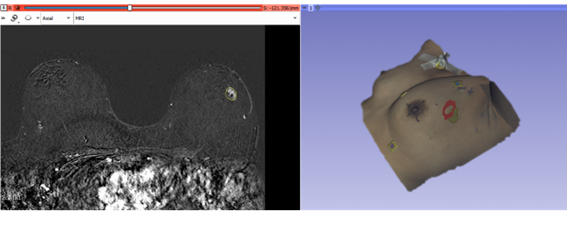

La técnica está implementada para su inclusión en una herramienta capaz de representar los modelos 3D de la escena intraoperatoria, incluyendo la superficie intraoperatoria, la posición estimada de la lesión y su proyección en piel. Fuente: UPM

La técnica desarrollada se ha implementado para su inclusión en una herramienta capaz de presentar al cirujano la escena intraoperatoria con modelos tridimensionales de la superficie y de la lesión, así como su proyección en la piel. De esta manera, se puede brindar una lectura rápida e intuitiva de la escena intraoperatoria para guiar la resección tumoral. Los resultados son prometedores y comparables con métodos existentes que implican cambios significativos en el protocolo deadquisición de imagen preoperatorio.